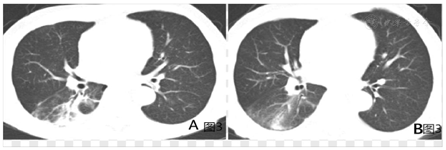

患者转入呼吸ICU后,积极给予呼吸支持治疗、抗感染、抗炎、补液、纠正电解质紊乱及保肝、护胃、营养支持等对症支持治疗,患者体温逐渐下降,大便情况好转,肝酶、肌酶、血小板指标逐渐好转,2020年9月28日神志转清,具体病情转归情况见表3,表4。2020年9月30日转出RICU至普通呼吸病房,10月8日复查胸部CT示右下肺炎症明显好转(图3A),病情稳定后于2020年10月18日顺利出院。11月20日来院复查右下肺炎症进一步好转(图3B)。